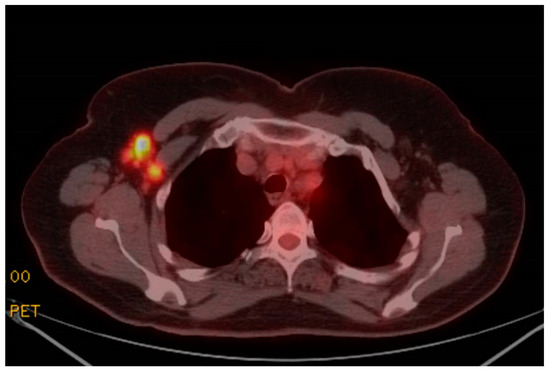

Increased FluoroDeoxyGlucose (FDG) Avidity Following COVID-19 Vaccination